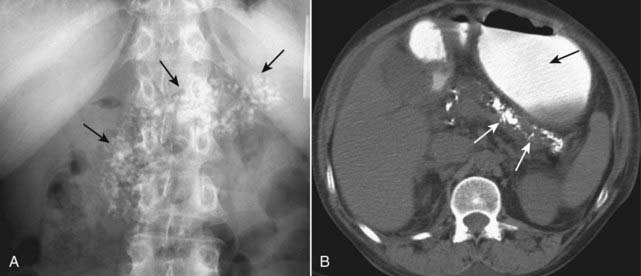

Figure 16-11 Chronic calcific pancreatitis, conventional radiograph (A) and axial CT scan (B).

A, A close-up view of the left upper quadrant of a conventional radiograph of the abdomen shows amorphous calcifications (solid black arrows) implying calcification in a solid organ or tumor. The anatomic distribution of the calcification corresponds to the pancreas. B, In another patient, a nonenhanced image of the upper abdomen shows calcifications distributed along the course of the body and tail of the pancreas (solid white arrows). There is oral contrast seen in the stomach (solid black arrow). These calcifications are pathognomonic of chronic pancreatitis, a chronic and irreversible disease that leads to atrophy of the gland and diabetes, occurring mostly secondary to alcoholism.